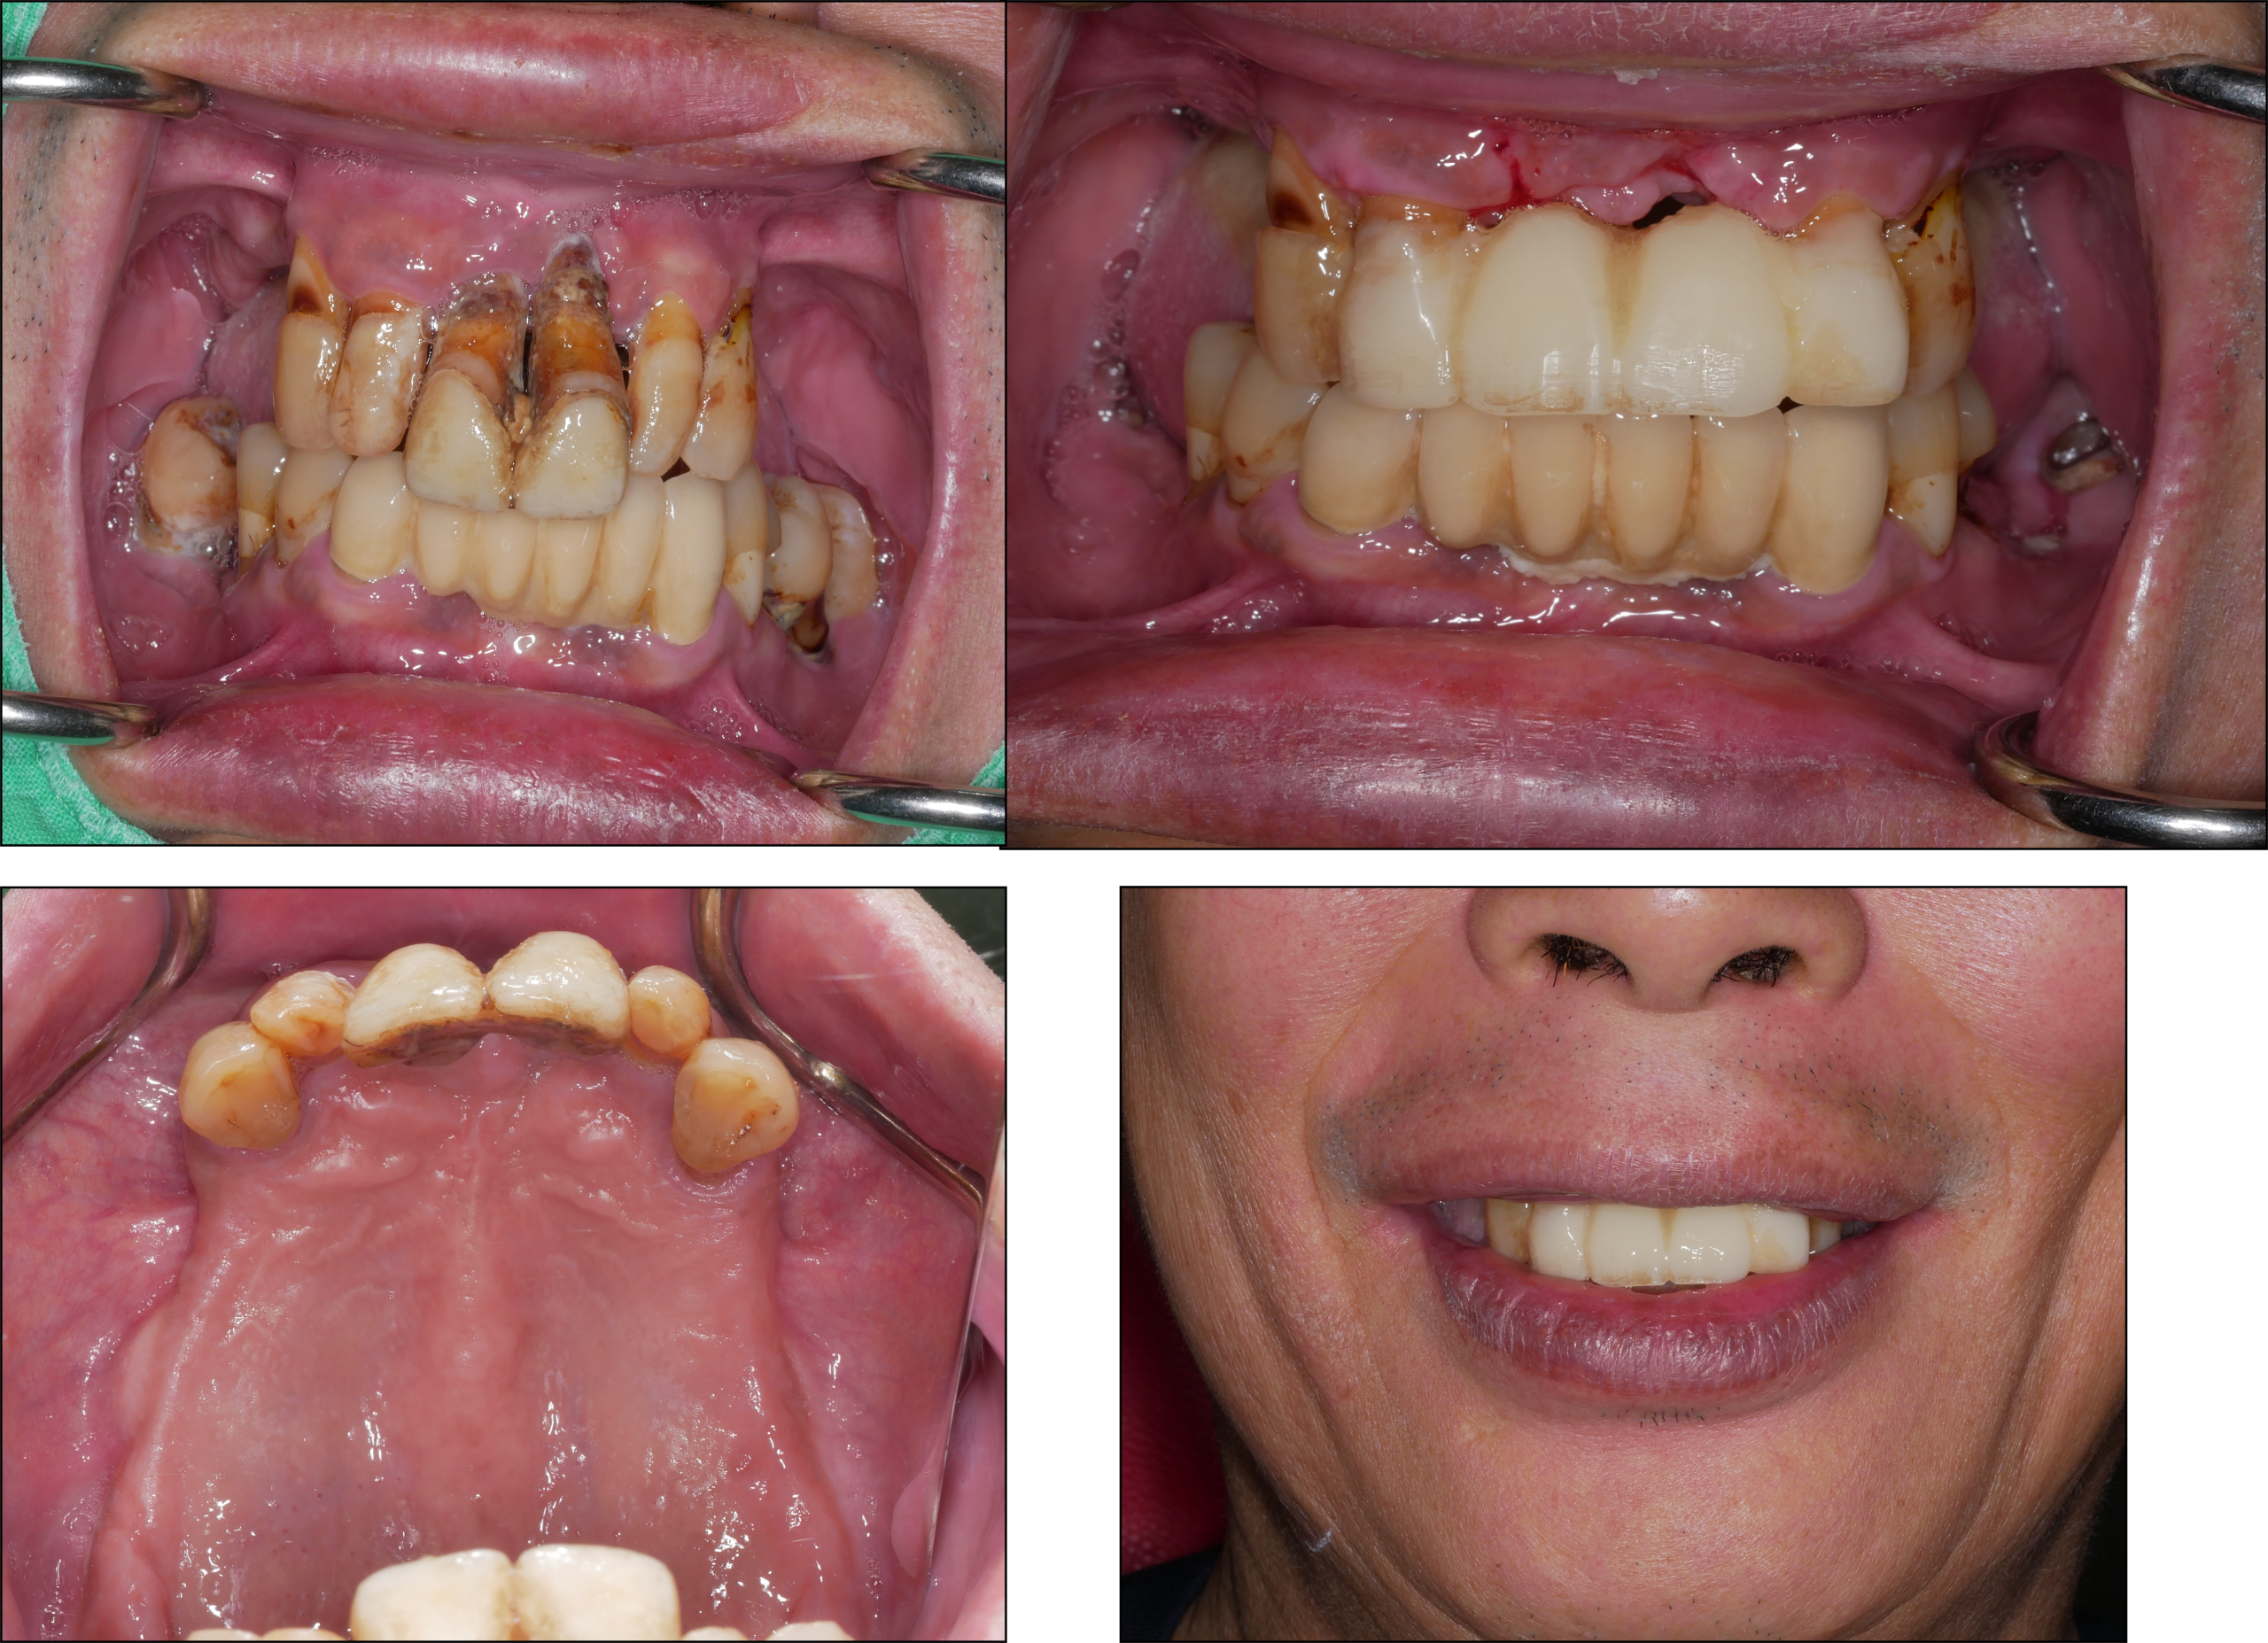

▍治療過程

處理過程:口腔衛生不佳,上顎骨後牙區鼻竇底Crestal bone很薄,前牙區basal bone也很窄。因此採用staged zygoma implants 治療方式。

變通原因:因前牙牙齒尚可支撐,先製作臨時假牙維持美觀。後牙區採取二階段植牙重建Zygoma implants手術,合併Sinuns augmentation減少Oroantral communication風險。

避免風險:男性,對牙真牙,不平衡咬合。staged approach可避免immediate loading喪失骨整合的風險,也可減少Zygoma implant loading後造成Oroantral communication 的可能性。staged approach可等待植體骨整合及隔絕Sinus membrane與口腔相通。等待期間還可加強口腔衛生教育。

1.Oral hygiene and disease control

2.11,21 ext. + 12-22 temp bridge

3.15,25 staged zygoma implant

4.UA contour GBR

15,25 staged zygoma implant surgery + sinus augmentation & UA contour GBR